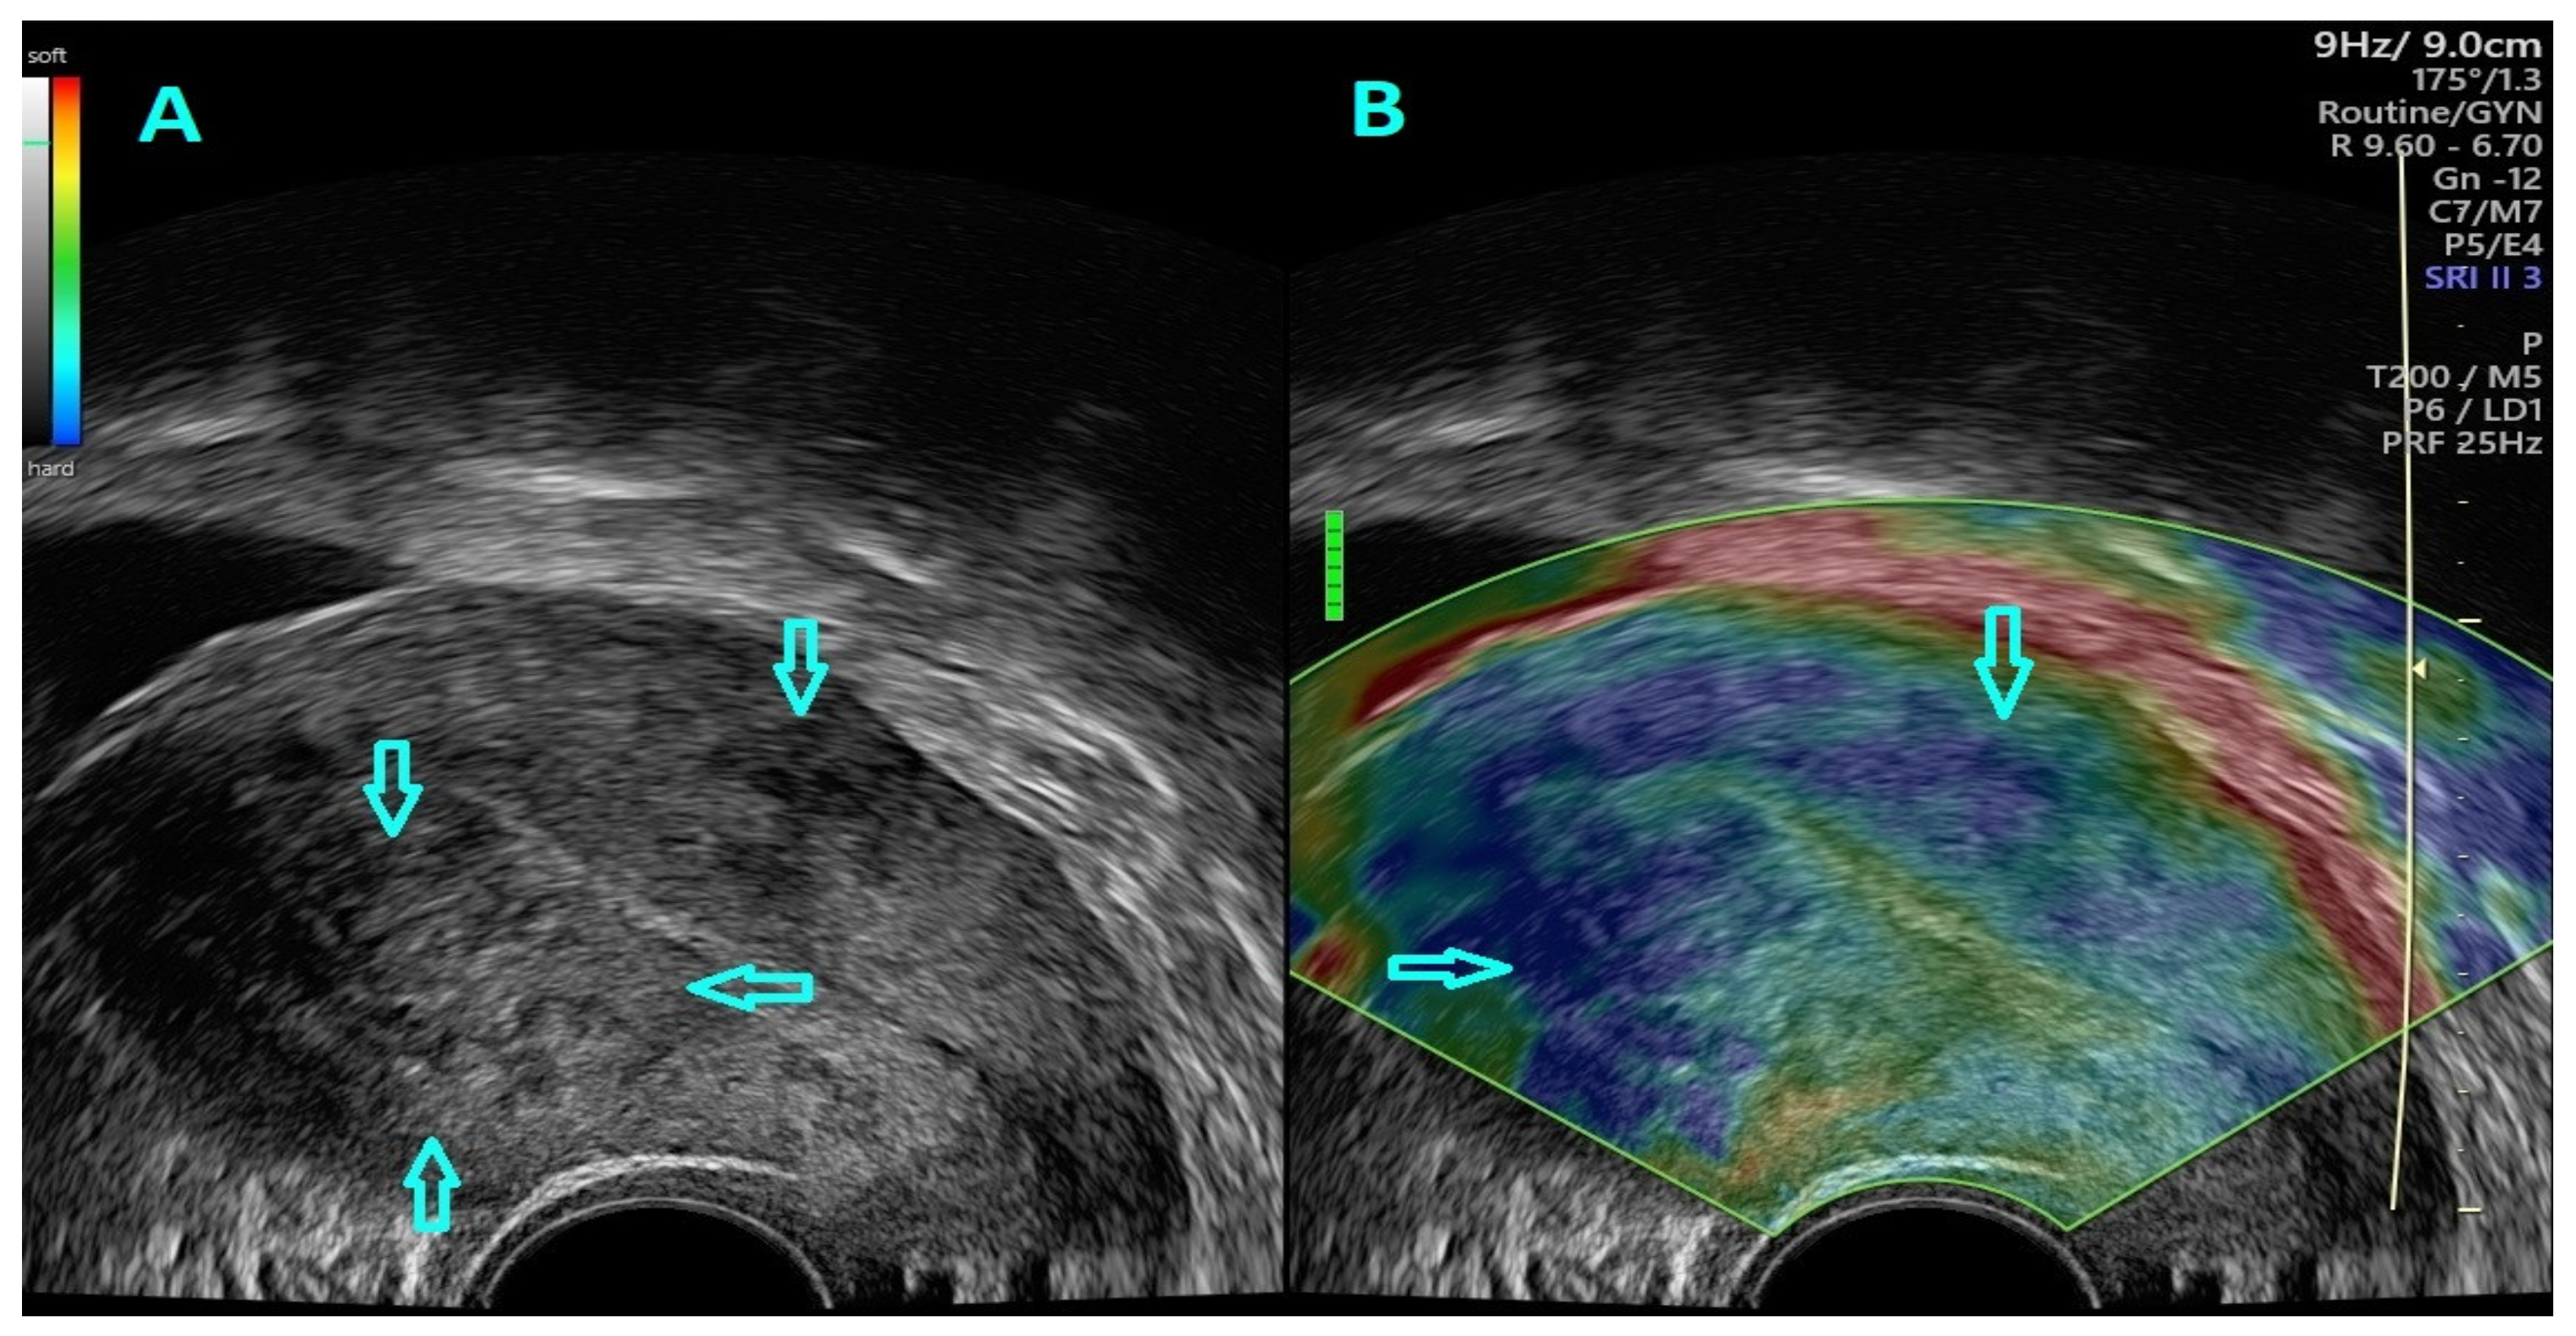

2.4. Strain Ratio Elastography Evaluation